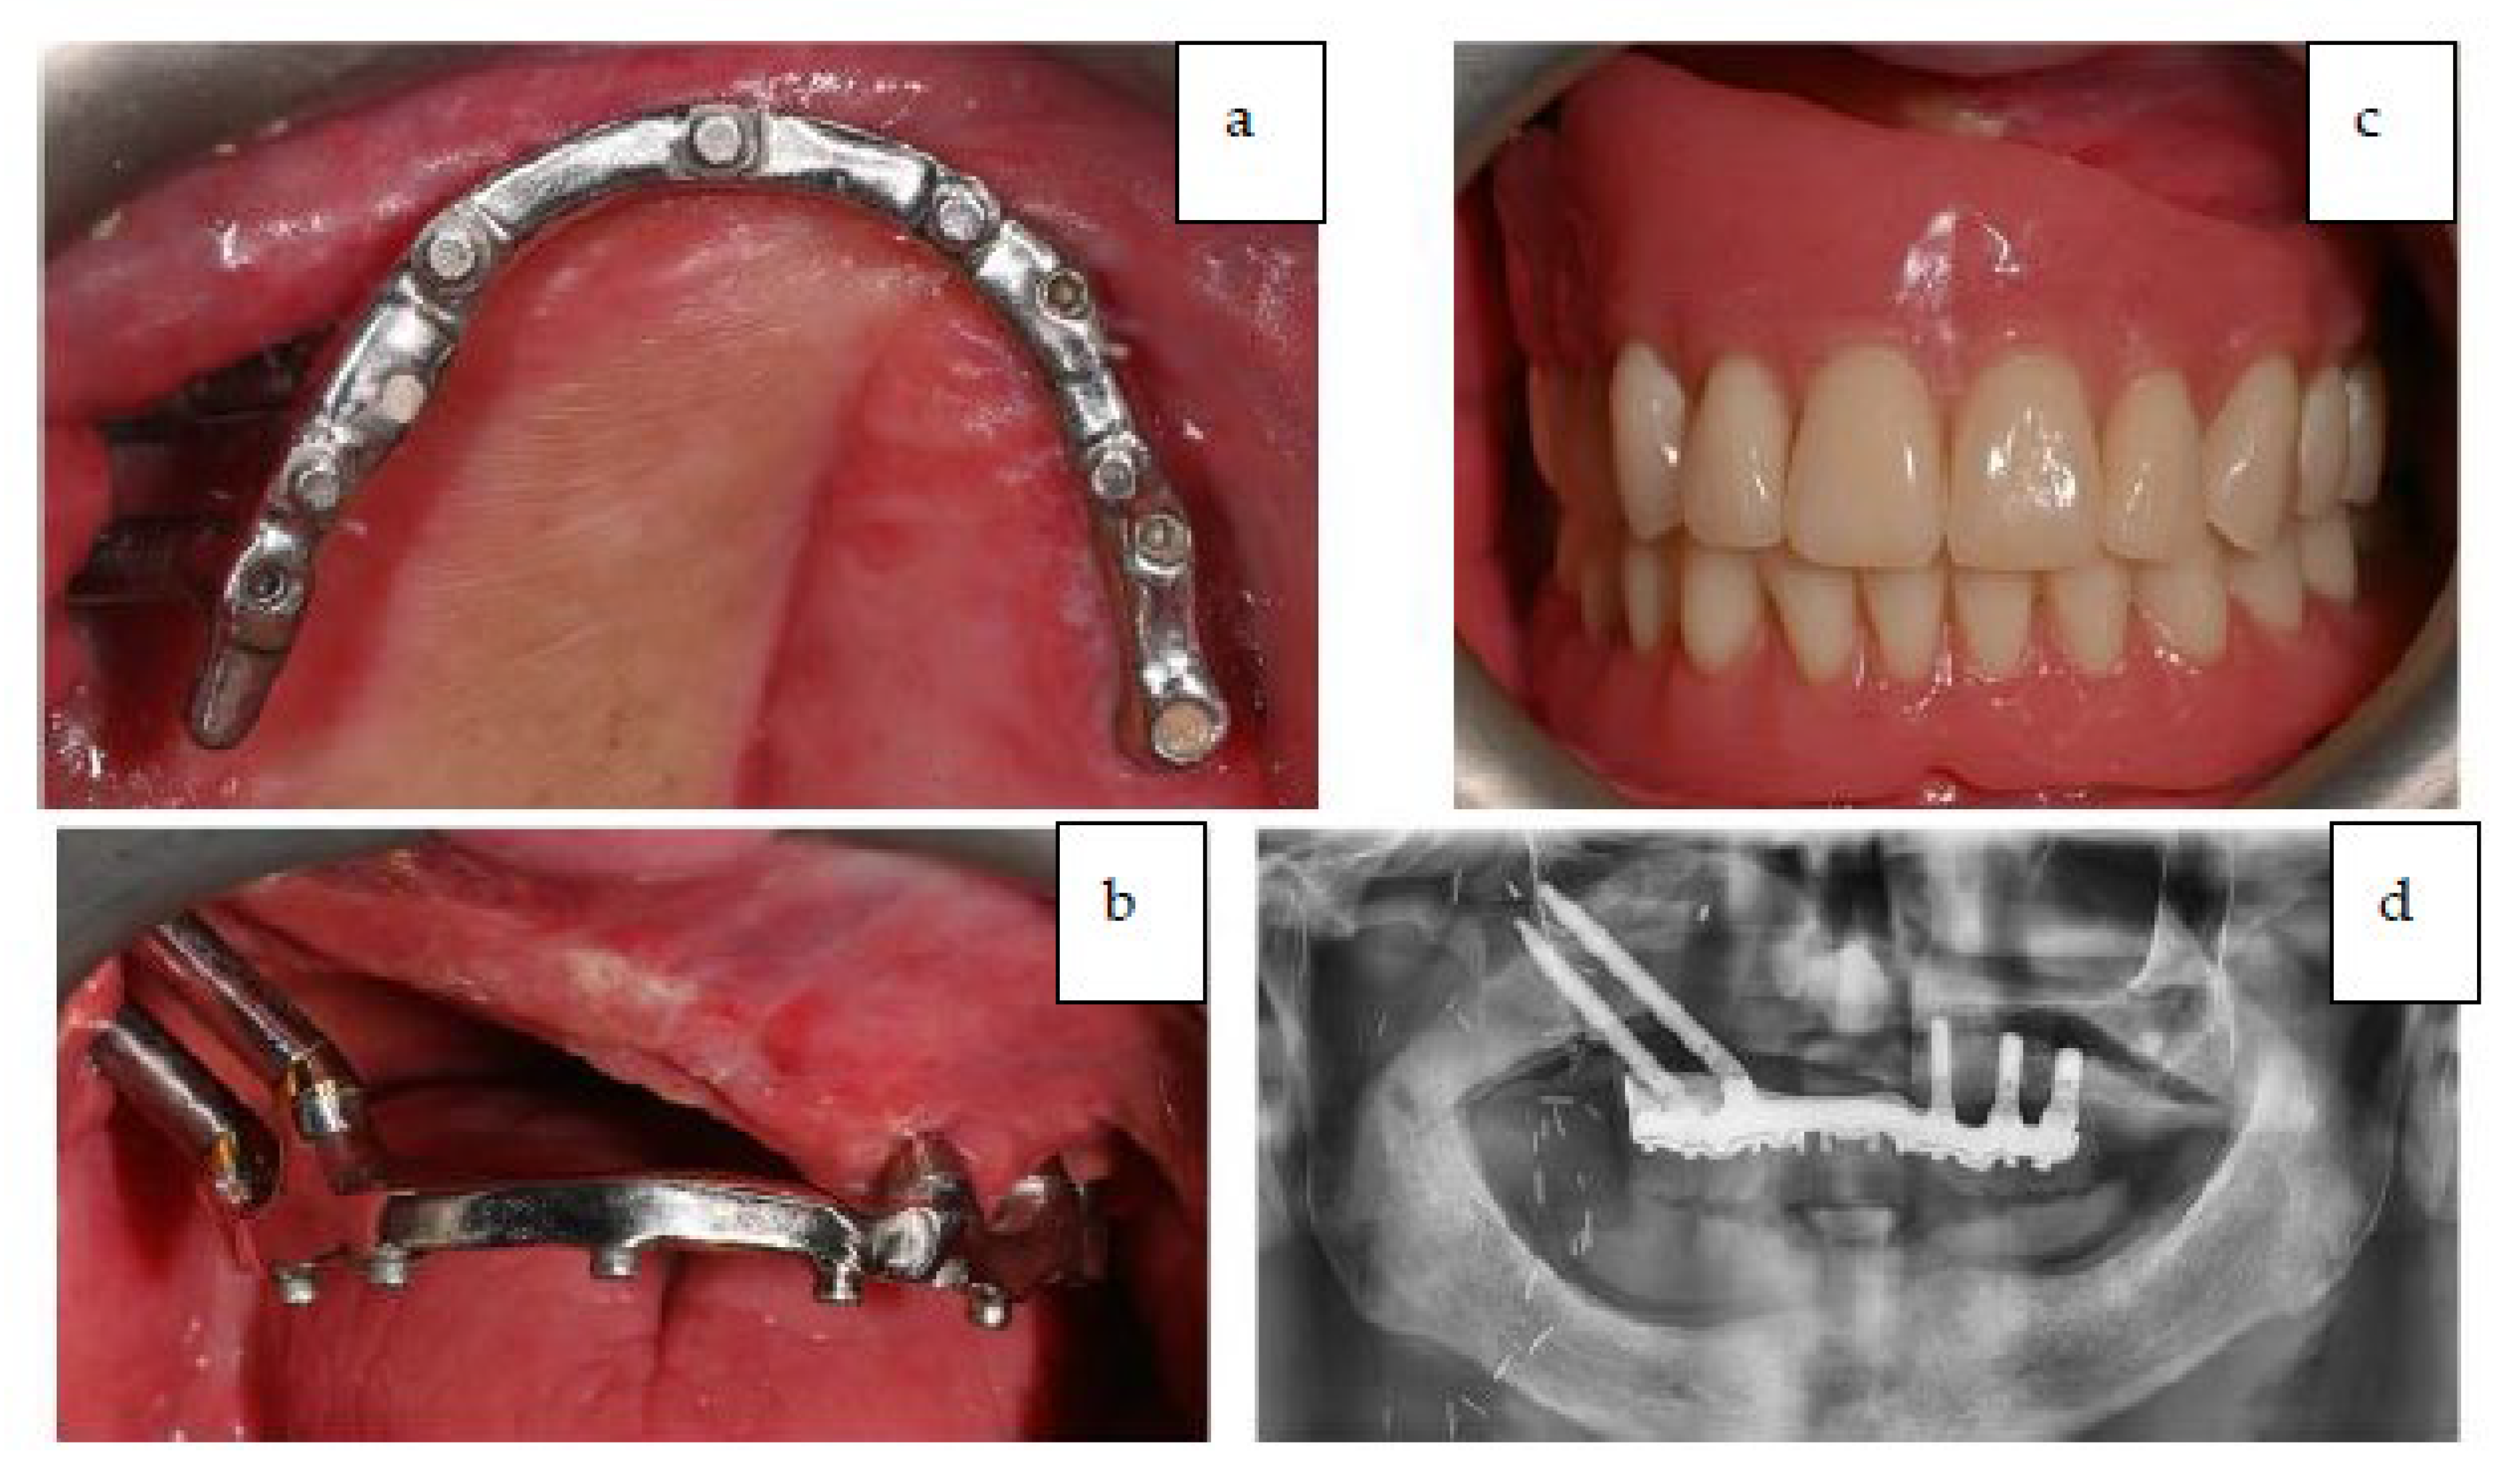

4. Surgical Technique

Post-Operative Report